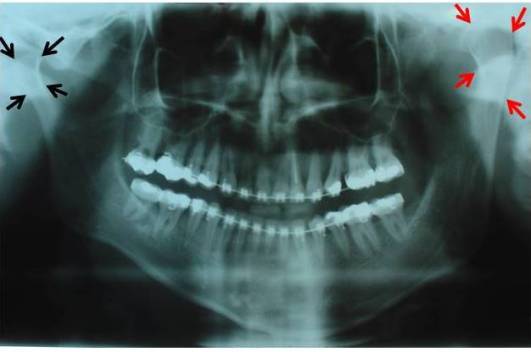

O processo condilar aumentado de tamanho, quando comparado ao côndilo oposto na radiografia panorâmica, é um achado frequente e muito importante. A mordida cruzada posterior do lado oposto ao côndilo afetado é uma característica clínica muito frequente, entretanto, em pacientes muito jovens, esta alteração oclusal pode ainda não estar presente. Por fim, a assimetria facial, que pode ser leve ou muito severa, caracterizando-se por um desvio do mento e da linha média dentária inferior para o lado oposto à hiperplasia condilar. Mudanças compensatórias podem estar presentes nas estruturas dento-alveolares da maxila e mandíbula, causando alterações transversas no plano oclusal.